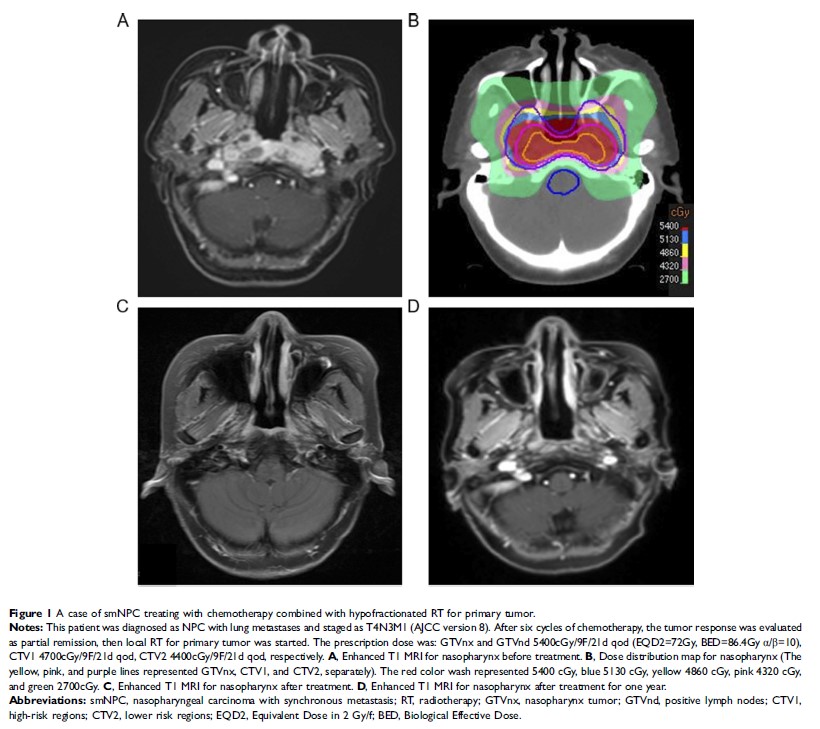

鼻咽癌同步转移的特征和新型治疗策略